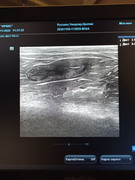

Сделали повторное узи 22.11. 2024 (первое было 09.11.2024). Высылаю фото и заключение.

Теперь ставят гидрометру и эндометрит. По мочевому мочекаменную.